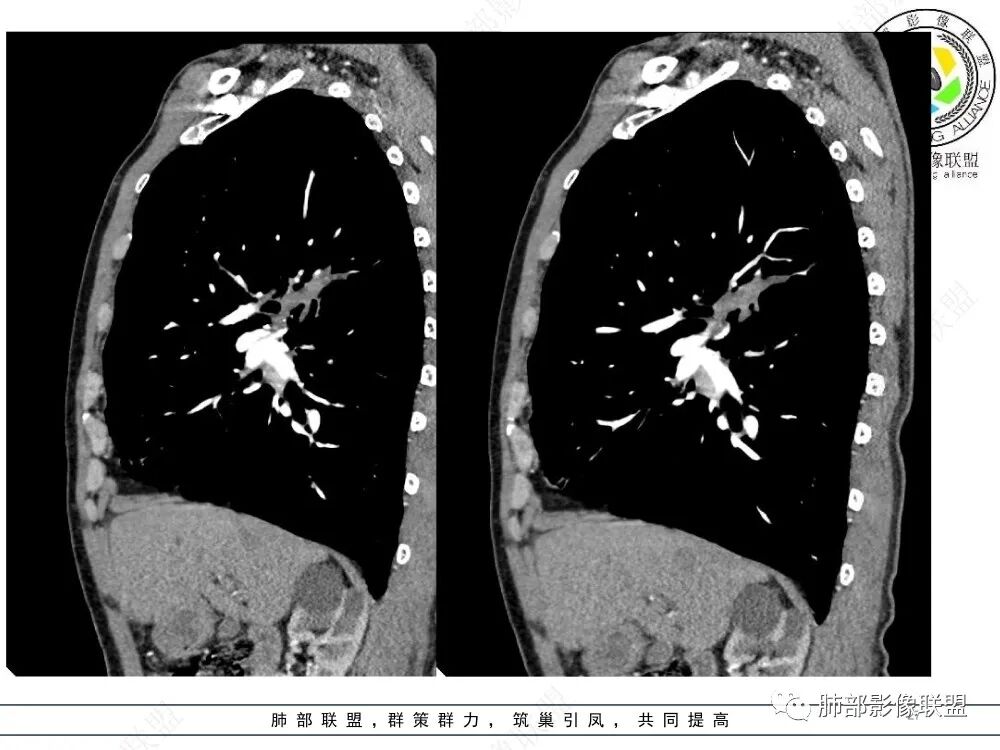

3、影像表现:肺气肿背景,右肺上叶后段支气管开口阻塞并见腔内软组织影轻度突向叶支气管,阻塞段以远支气管及分支扩张填塞呈指套样改变,轻度不均匀强化,外周点片影,符合阻塞性炎性表现,现有图像资料未见明确肺门纵膈淋巴结增大。

上图,鳞癌,腔内软组织占位,局部膨大,不均匀强化,伴远端粘液栓。